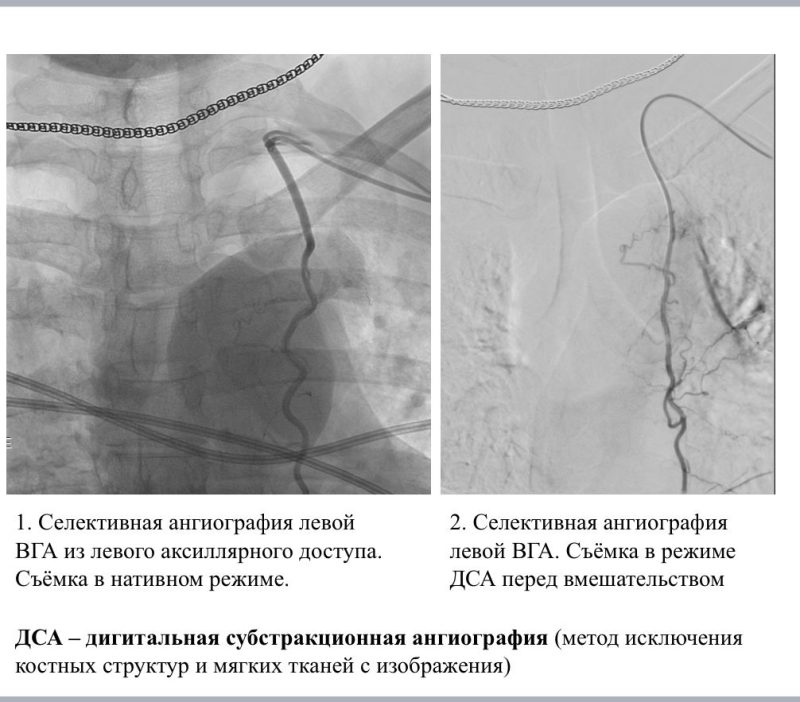

Ее лечили несколькими методами: хирургическим, химиотерапевтическим и проводили селективную внутриартериальную химиоинфузию (введение препарата в артерии, питающие опухоль).

На фото-рентгеновские снимки. Черные линии-сосуды, по которым катетером вводится препарат к самой опухоли.